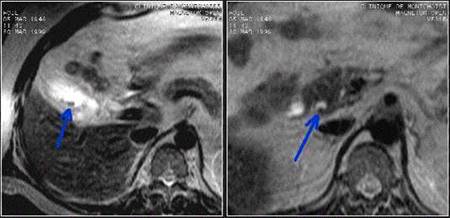

Fig 6 Risonanza Magnetica addome superiore . aumento dello spessore di parete della colecisti e presenza di formazioni litiasiche